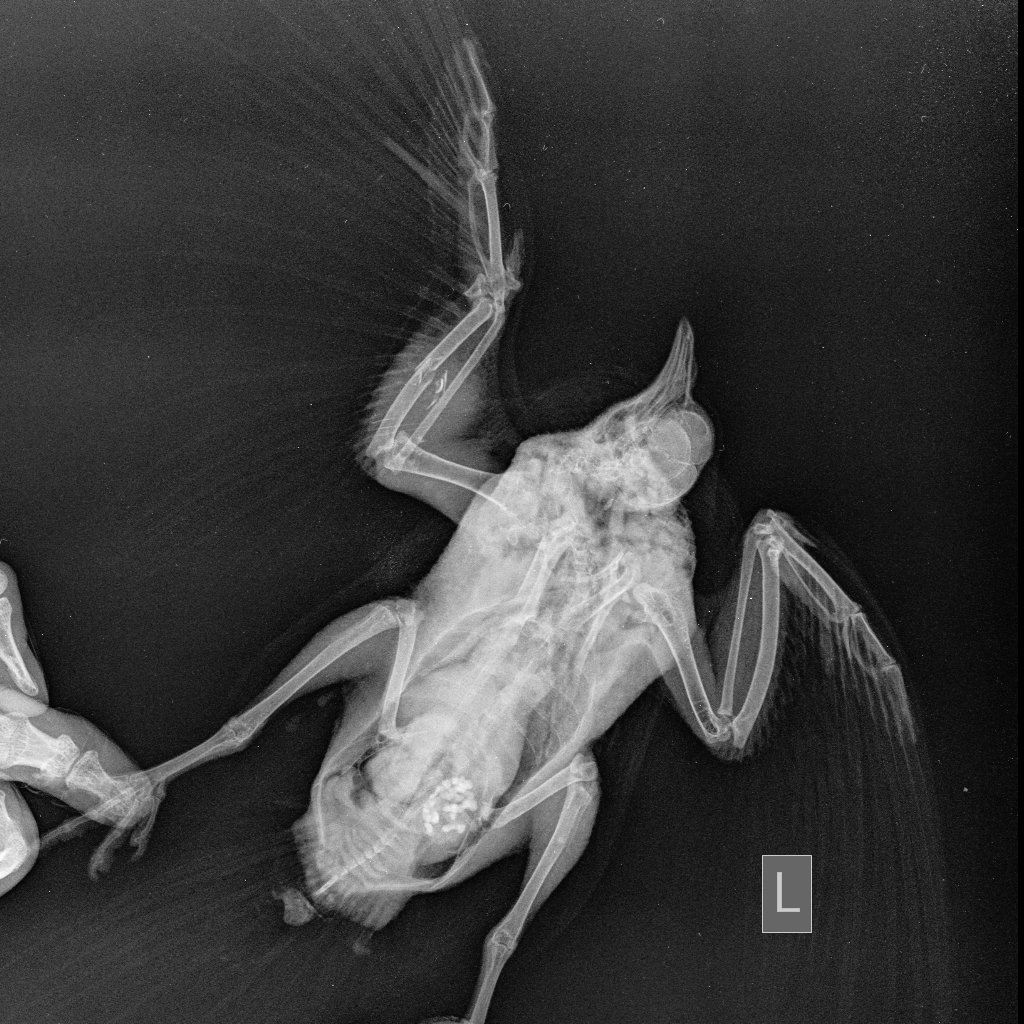

Zosia Опубликовано 29 июля, 2021 #15 Опубликовано 29 июля, 2021 Вам надо сделать еще раз снимок, с аккуратно и полностью раскрытым поврежденным крылом. Фиксировать к основанию (над кассетой) бумажным скотчем, придерживать крыло у плеча. Потому что на вашем первом снимке- полный многооскольчатый перелом локтевой кости с малым смещением, а вот лучевая кость выглядить выбитой (оторванной), что озанчает внутрисуставный перелом...Но т.к. крыло снято не в раскрытом состоянии- степень повреждения оценить трудно. Что там с легкими- а что-то есть- так же плохо видно. С успехом это м.б. микоплазмоз, или клебсиелльная пневмония, или тупо аллергическая реакция на что-то. Глубокий мазок из глотки и помет- и красить по Циль-Нильсену. Смотреть КУМ и криптоспоридии. Ну и банальный общий анализ помета (копрограмма) Пока основная терапия- снятие боли (НПВС), травматин, миорелаксант можно (толперизон). Фиксация - магкая, в сетчатый трубчатый бинт, со свободным здоровым крылом. Вот аткого типа: https://public.fotki.com/Shemlik/bae5/b70c.html https://public.fotki.com/Shemlik/bae5/2.html#media https://public.fotki.com/Shemlik/bae5/3.html#media

Cara Mia Опубликовано 4 августа, 2021 Автор #17 Опубликовано 4 августа, 2021 Добрый день! Снимки нового рентгена голубя были сделаны в клинике "Главное Хвост". Лечащий врач этой клинике после осмотра и на основании этих снимков сделала такую выписку (фото) с диагнозом (диф.) Аэросаккулит, (диф.) Аэроцистит. По перелому сказала, что оба крыла работают, оно начинает срастаться, но необходимо извлечь остатки раздробленной кости, для чего нужна операция, а вывихи вправлять в Беларуси не могут. Посоветовала записаться на прием к главному врачу-орнитологу клиники А. Полозу, который до 14.08. находится в отпуске. Назначены следующие препараты: 1. Амоксициллин 250 мг - внутрь по 1/16 содержимого капсулы 1 раз в день, на протяжении 10 дней. 2. Мелоксидил сусп. - внутрь по 0,1 мл 1 раз в день, на протяжении 10 дней. 3. Нистатин 500000 ед. - внутрь по 1\6 таблетке 2 раза в день, на протяжении 14 дней. 4. Карсил - внутрь по 1/10 таблетки 1 раз в день на протяжении 14 дней. Не входит ли это в противоречие с уже существующим назначением другого врача?: 1. Ципрофлоксацин, 250 мг, внутрь по 1/10 таблетки 2 раза в день 3 недели (ПРОДОЛЖЕН С 14 ДО 21 ДНЯ ПОСЛЕ ПЕРВЫХ СНИМКОВ РЕНТГЕНА) Курс начат 22.07 Курс будет закончен 12.08 2. Мелоксикам 7.5 мг, внутрь по 1/10 таблетки 1-2 раз в день, 7 дней, далее по состоянию Курс начат 20.07 Курс закончен 27.07 3. Метронидазол 250 мг внутрь по 1/8 таблетки 1 раз в день 5-7 дней Курс начат 20.07 Курс закончен 26.07 4. Нистатин 500000 ед. внутрь по 1/4 таблетки 2 раза в день в течение месяца (ДОБАВЛЕН ПОСЛЕ ПЕРВЫХ СНИМКОВ РЕНТГЕНА) Курс начат 22.07 Курс будет закончен 22.08 5. Празицид, суспензия для котят внутрь по 0.3 мл 2 раза с интервалом 14 дней Курс начат 23.07 Курс будет закончен 07.08 6. Стронгхолд 1/2 пипетки 2 раза с интервалом 21 день Курс начат 18.07 Курс будет закончен 07.08 СОСТОЯНИЕ: Голубь стал беспокойным, постоянно пытается выбраться из контейнера, часто машет крыльями. Ест хорошо, по назначению врача (каши, семена подсолнечника, льна), морковь и салат добавляю,но он не ест почти). Несколько дней назад цвет стула изменился на зеленый (фото), врач связала это с большим количеством медпрепаратов. Во время кормления лекарствами через пипетку сейчас вертит головой, оказывает сопротивление (раньше такого не было). Также при приближении руки убегает, вырывается и немного "кряхтит" (так, как это делают утки). Звук могу скинуть, если нужно. На приложенных гифках он сегодня после приема у врача, в состоянии стресса. Также Ахова птушак Бацькаўшчыны (@apb_birdlife_belarus посоветовала мне связаться с Зоей Кенько. Спасибо ей большое, что она сразу же ответила, и помогла с расшифровкой назначений, а также с контактами хороших хирургов и терапевта для проведения операции. АНАЛИЗЫ: На анализы есть возможность записаться в субботу, этого врача советуют консультант Зоя Кенько и Валерия Сороко (ВетТаргет). Стоит ли ждать продолжать курс, менять курс лечения, не дожидаясь анализов (мазок из зоба, копрограмма) до субботы хорошего врача (Вересовая Екатерина)? К сожалению, в других клиниках или не делают эти анализы, или (по отзывам волонтеров и хозяевов) делают их не совсем качественно. Прошу Вас помочь с диагностикой голубка и спасибо большое за помощь! @Zosia @OFA @маленький принц

OFA Опубликовано 7 августа, 2021 #19 Опубликовано 7 августа, 2021 @Cara Mia назначения вполне адекватные, следуйте назначению доктора. Крыло, боюсь, это не вылечит( Висит крыло сильно, скорее всего есть перелом в плечевом суставе, но может и воспаление. Зося смотрела 2 рентген?

Cara Mia Опубликовано 7 августа, 2021 Автор #20 Опубликовано 7 августа, 2021 Зося @Zosia ещё не смотрела. Врач сказала, что кости уже срастаются.

Zosia Опубликовано 8 августа, 2021 #21 Опубликовано 8 августа, 2021 Срастаются. Будет некоторое ограниечение в функционале, но рабочее. А отломок- может и сам отторгнуться, через образовавшийся (в идеале) свищ. Остеогенон проперйте. 1/20 капсулы в сутки, три недели.